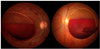

Qual o primeiro achado no fundo de olho na hipertensão intracraniana?

Ausência de pulso venoso

Hemorragia sub-hialoide no fundo de olho?

Hemorragia subaracnoide

Qual a complicação da HIC idiopática?

Perda visual